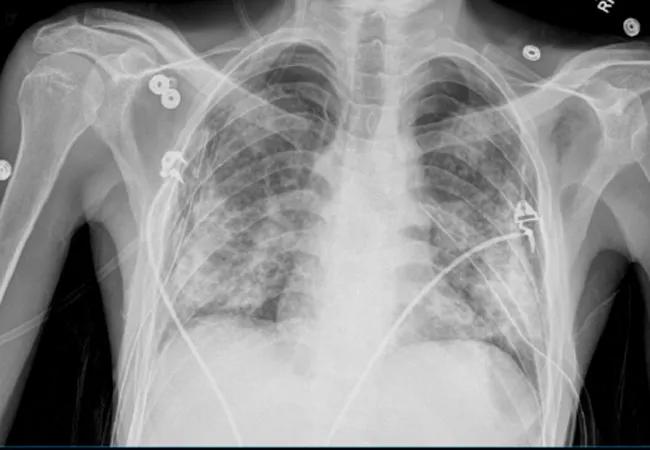

Many hospitals obtain chest X-rays (CXR) daily on patients in their intensive care units (ICU), though it has been over a decade since this practice was recommended. The American College of Radiology (ACR) stopped recommending daily CXR in 2008 after much research showed that using on-demand imaging does not impact ICU length of stay, duration of mechanical ventilation, morbidity or mortality, and can negatively affect patients’ sleep and radiation exposure rates. The ACR strengthened its stance on daily CXR to “usually not appropriate” in 2011 and 2014.

But for most clinicians and hospitals, including Cleveland Clinic, daily CXR remained standard practice. We averaged 375 portable CXR per day across the health system in 2018. Given the data supporting on-demand images, we sought to move away from this practice across all Cleveland Clinic hospitals.

Our first step was to meet with all key stakeholders, including intensivists, surgeons, pulmonologists and radiologists. We then altered the options for chest imaging in the electronic health record so that providers could only order daily CXR for patients with cardiac support devices or who had undergone cardiac and thoracic surgery. Providers were also required to indicate a specific reason for the need in this population. We analyzed data from the pre- and post-intervention periods with a two-sample t-test.

Average daily portable CXRs decreased 23.5 percent overall (P < 0.001), and average overnight CXR decreased 36.6 percent (P < 0.001). The CXR volume during rounding hours did not increase in compensation, and actually decreased by 15.8 percent (P < 0.001). The initiative did not result in any reported harm events or delays in care. I presented these results at the 2019 Society of Critical Care Medicine Annual Congress.